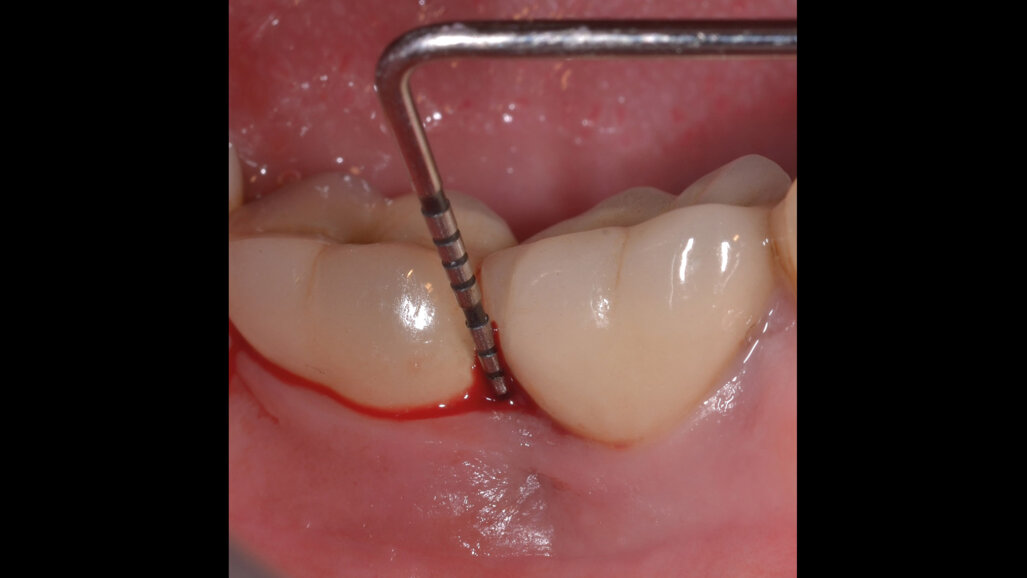

Il paziente, di sesso maschile e di 48 anni di età, è in buone condizioni di salute generale ma, a distanza di 10 anni dall’inserimento, presenta due impianti endossei, in posizione 4.6 e 4.7 con uniforme perdita ossea e con sondaggi di profondità variabile tra 6 e 9 mm accompagnati da sanguinamento, con tessuti marginali che mostrano importanti aspetti infiammatori, causa di sintomatologia dolorosa per il paziente (Figg. 1a-f).

I siti interessati sono stati strumentati per via non chirurgica, utilizzando strumenti manuali, strumenti ultrasonici e air polishing con eritritolo. Al termine della seduta è stato applicato il gel di ozono (Ozosan Gel - Bioactiva) all’interno delle tasche, lasciando agire il dispositivo per 8 minuti, quindi eseguendo lavaggio con soluzione fisiologica. Il post-operatorio ha avuto un decorso privo di dolore con rapida remissione della sintomatologia soggettiva. Il paziente è stato inserito in un programma di mantenimento parodontale trimestrale. A distanza di 6 mesi dal trattamento non chirurgico della perimplantite, i siti si presentano stabili con profondità di sondaggio ridotta tra i 3 e i 5 mm con assenza completa di sanguinamento al sondaggio (Figg. 1g-m).